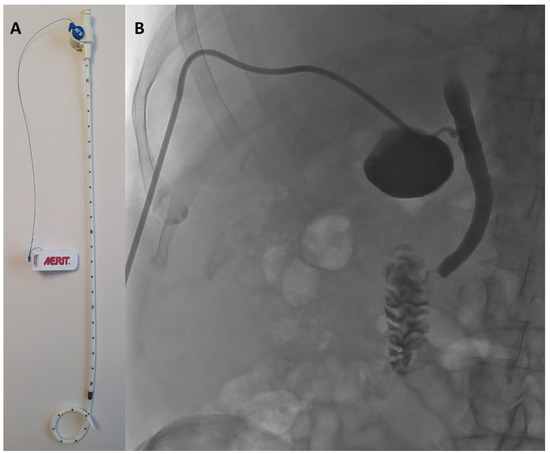

PTGBD was performed under sterile conditions by an interventional radiologist using either US or CT guidance, depending on anatomical considerations and operator preference. PTGBD was done under local anesthesia and/or sedation according to patient comfort and cooperation. Under imaging guidance, a transhepatic approach accessed the gallbladder, followed by placement of an 8.5 French pigtail catheter (Re-solve®, Merit Medical Systems Inc., 1600 West Merit Parkway, South Jordan, UT, USA) for continuous drainage. Correct positioning was confirmed by contrast injection and imaging (Figure 1).

Figure 1.

(A) 8.5 French pigtail catheter (Resolve®, Boston Scientific). (B) confirmation of the correct position of the drain by contrast injection and imaging.